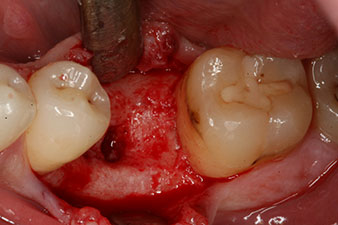

However, six weeks after the extraction incomplete ossification was found after preparation of the mucoperiosteal flap in the region of the former mesial alveolus.

The implant was placed as planned after thorough removal of the granulation tissue (blueSky, bredent).

These values could have indicated open healing or even immediate restoration. Due to the insufficient crestal bone volume at the implant, the region was augmented with the bone chips collected during preparation of the implant bed and sutured to exclude saliva.